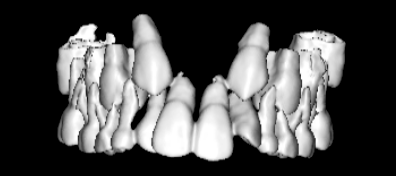

治療開始時

FX(フェイシャルアキシス)は85度なので東洋人の平均値に近く、下顎が前方に過剰成長するリスクは強くはありません。

しかしやはり上顎は劣成長で、下顎が優位な状態ではあります。

上下顎のギャップはありますが、顔面自体の幅径は良好な値を示していますので、スペース不足は拡大することによって解決できポテンシャルはあると考えられます。

左右の非対称もさほど強くありません。